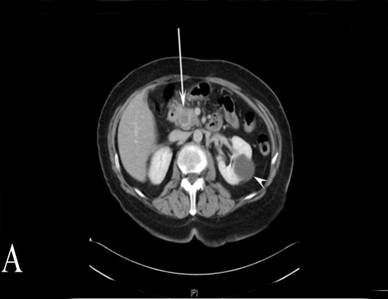

A 68-year-old woman presented with a three-month history of worsening abdominal pain, weight loss and jaundice. She had been diagnosed with type 2 diabetes three months prior to onset of symptoms. The patient’s past medical history included hypertension, asthma, diverticular disease, hypothyroidism, and a previous cholecystectomy. A CT and MRI scan of the abdomen showed an obstructing mass within the uncinate process of the pancreas and a second infiltrative mass in the tail of the pancreas encasing the splenic vein (Figure 2A, 2B). The uncinate process mass was causing a clear “double-duct” sign. An ERCP was attempted, but it failed and a percutaneous transhepatic biliary drain was inserted to relieve the jaundice prior to surgery. Her CA 19-9 was also negative. Both pancreatic tumours appeared resectable and following an MDT discussion a total pancreatectomy was performed. On pathology, both lesions proved to be necrotic masses with granulomatous inflammation and vasculitis, involving the common bile duct (the central one). Ziehl-Neelsen staining for mycobacteria and PAS for fungi was negative. Again, WG was considered the most likely cause for the observed histological features. CT of facial sinuses and lung function tests were again normal. She was p-ANCA positive (Anti MPO Ab= 8.8u/mL; normal range<3.4u/mL). There was no history of photosensitive rash, mouth ulcers or Raynaud’s disease. She has suffered from some morning stiffness lasting a few hours, but has not had any nosebleeds, sinus congestion or nasal crusting.

Figure 2. A. CT image depicting a mass at the uncinate process of the pancreas. The white arrow shows the mass. The white arrow head shows a cyst of the left kidney. B. CT image from the same patient showing the second mass at the tail of the pancreas in close proximity with vessels of the splenic hilum. The white arrow shows the mass. |